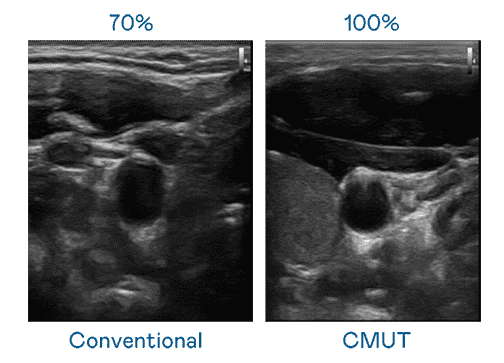

CMUT 技术是一种用电容式微机电元件来产生超音波讯号的技术。。。。与传统 PZT 压电式技术相比,,,,CMUT 频宽增加 30%,,,更宽频的超音波讯号让影像解析度大幅提升,,,是实现高影像品质医疗超音波扫描、、、促进精准医疗发展的关键技术。。

大频宽带来超清晰影像

超音波影像的解析度高低,,,首先取决于探头能发出的讯号频宽。。。红龙扑克 CMUT 可提供高清晰的超音波讯号,,提供高频宽、、、、高灵敏度、、、影像纹理细节更高的超音波影像,,,,协助医护人员缩短影像判读时间及利用精准的医疗影像进行诊断。。。。